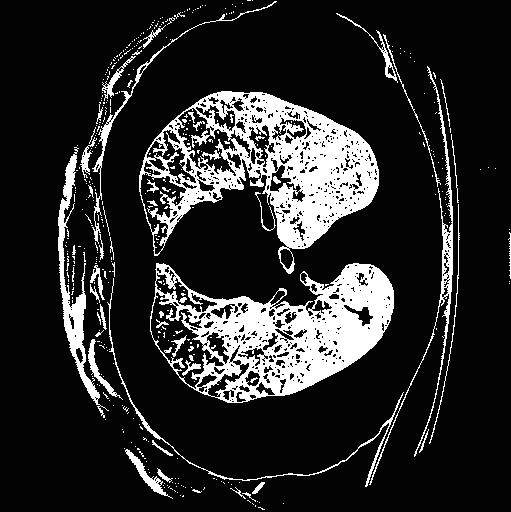

Top row: An image slice demonstrating the lung Isolation process, enacted on a low dose spiral CT scan taken from the LIDC-IDRI database.

- Abstract: An exploration of whether conventional detection methods of lung cancers in low dose spiral CT scan could be improved using curvature features. In general, a large source of inaccuracy in detection rates can be attributed to irrelevant anatomical structures such as blood vessels. Often these irrelevant anatomical structures have different shape characteristics from lung nodules. For example lung nodules tend to appear bloblike as oppose to blood vessels, which appear cylindrical, or organ walls, which appear planelike. These curvature features were determined using eigenanalysis of the local second order image Hessian of each voxel, where the principal values are indicative of the local shape and provide more information than analysis performed on first derivatives alone.

- Method Overview: In each CT scan, the internal 3D lung volume was isolated using standard thresholding of pressurevalues ranges associated with lung parenchyma. The remaining voxels were conjoined using a connected components method, implemented through a union-find method, with small and isolated components removed. The remaining gaps were filled in using a standard 3D image closure method. First and second order partial derivatives were computed using Deriche filters, chosen for their stability and suitability in medical image scans. Then, for each of the voxels in the internal volume of the lung the local second order Image Hessian was generated and analyzed for preferred directions using eigenanalysis. This information was then used to weight the contribution of each voxel to standard lung nodule detection methods, to determine if giving stronger weight to voxels with local blob-like shape improved detections results.